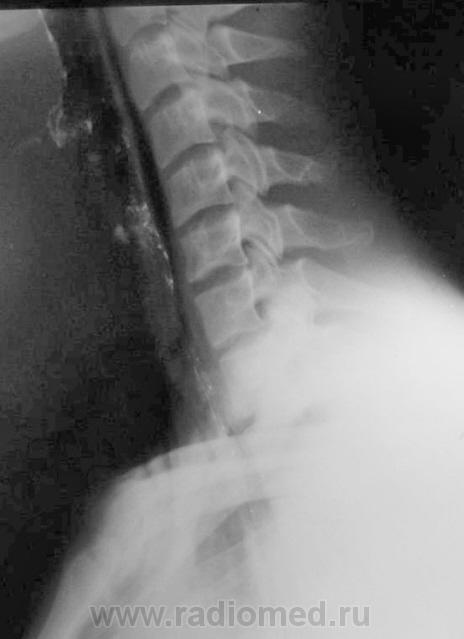

Молодой человек получил удар в шею. Был доставлен в травмпункт, дан барий для исключения перфорации пищевода.

Перфорации похоже нет, но есть другое...

Это чем же его ударили? Я так понимаю, ограниченный пневмоторакс слева  + эмфизема мягких тканей шеи?

Шейный кифоз настораживает.Отсутствие легочного рисунка в верхней доле левого легкого с краем легкогоЭмфизема мягких тканей шеи..Согласна с коллегой.Пару лет назад по кифозу ШОП, увеличению превертебрального пространства и столбу воздуха поставили разрыв пищевода.Дали  контраст-подтвердили.

Затекания контраста за пределы пищевода на представленных рентгенограммах не выявлено. Нет фазы тугого заполнения. Левосторонний пневмоторакс.

Да, ЛОРа 100% надо на консультацию, т.к. барий затек не туда.